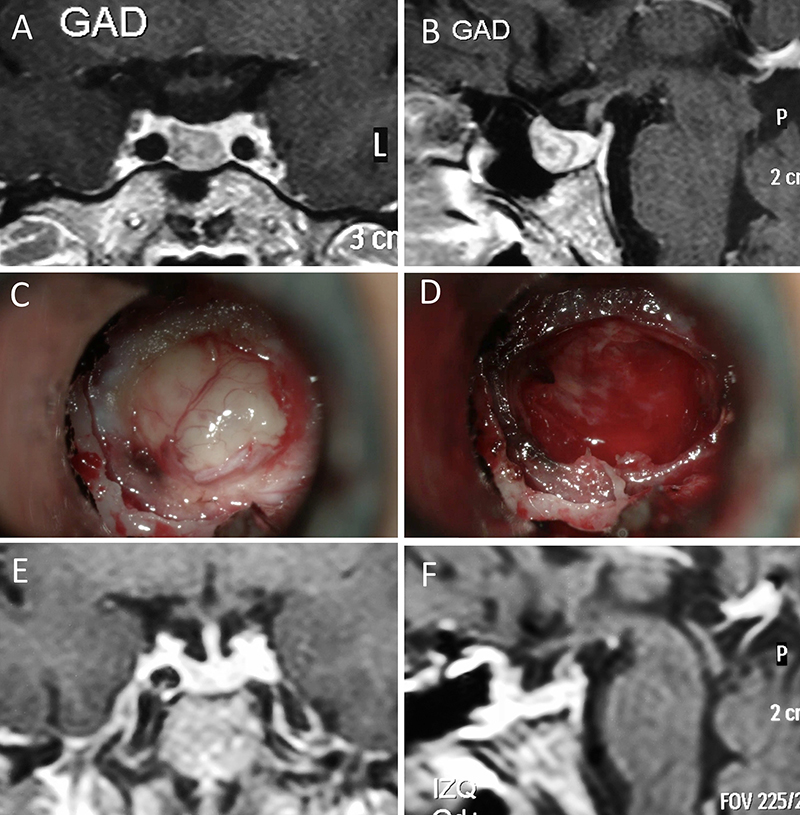

Figura 3: Macroadenoma no funcionante en un hombre de 64 años. El paciente presentó en el preoperatorio déficit visual que mejoró tras la cirugía. A-B: RM preoperatoria; C-D: intraoperatorio; E-F: RM postoperatoria.

Figura 4: Macroadenoma no funcionante en mujer de 32 años. La paciente presentó en el preoperatorio déficit visual que mejoró tras la cirugía. A-B: RM preoperatoria; C-D: intraoperatorio; E-F: RM postoperatoria.